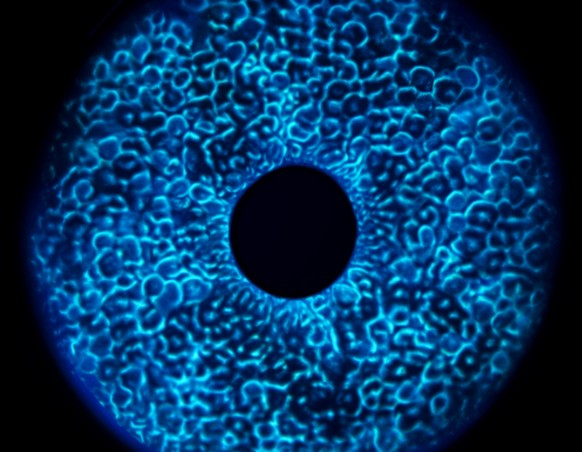

1. 裂隙灯显微镜检查

用途:观察角膜、结膜等结构的细微变化

方法:通过裂隙灯显微镜放大眼部,提供高分辨率图像

特点:能清晰显示角膜表面的细微病变,形成光学切面,使屈光间质的不同层次、甚至深部组织的微小病变也清楚地显示出来

5. 角膜地形图分析

用途:定量描述角膜表面形态特征

方法:利用特殊设备采集角膜图像,经计算机处理生成报告

特点:辅助诊断圆锥角膜等疾病,可显示角膜表面形态